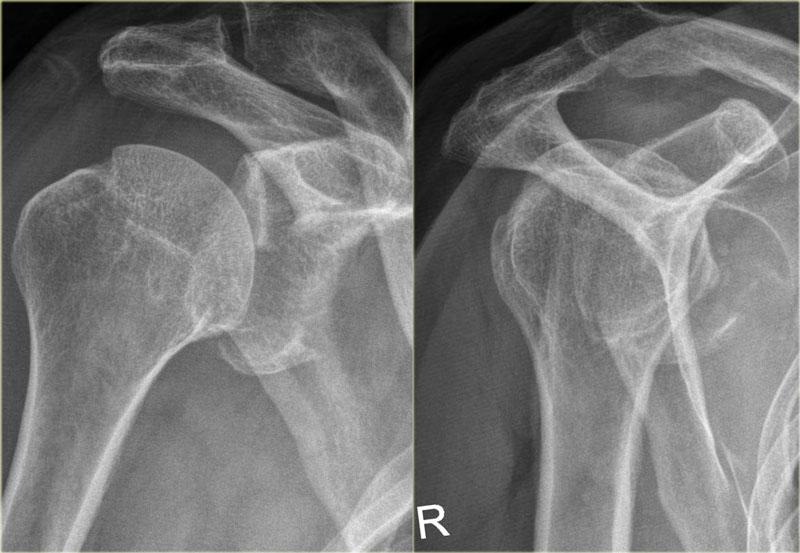

Đây là hình ảnh sau nắn chỉnh.

Lưu ý đường gãy rất lớn của bờ ổ chảo kèm di lệch mảnh gãy.

Trên tái tạo mặt phẳng chếch vành tai và mặt phẳng đứng dọc, mảnh gãy di lệch của bờ ổ chảo được thấy ở vị trí 3-6 giờ.

Trên hình ảnh mặt phẳng vành tai, quan sát thấy một khuyết xương Hill-Sachs lớn.

Đây là khuyết xương do hậu quả của sự va đập bờ ổ chảo vào chỏm xương cánh tay.

Tái tạo 3D của tổn thương Bankart xương lớn tại vị trí 2 – 6 giờ.